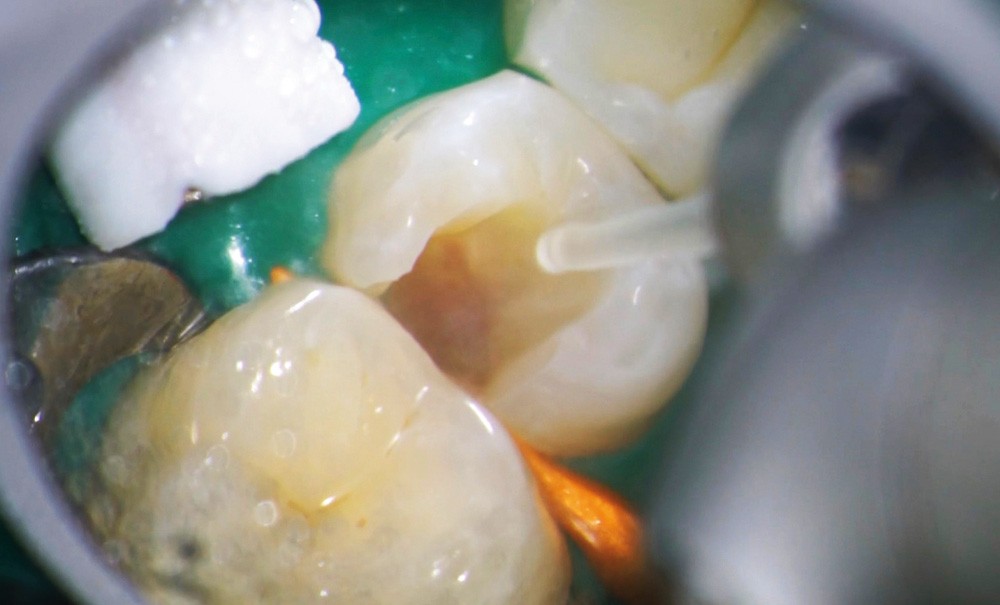

Le laser Er:YAG va permettre une élimination des débris en surface, une stérilisation, avec comme irrigation de l’eau stérile [36] et en coupant le spray, une hémostase avec la formation d’une couche de coagulation [37] propre à la formation d’un pont dentinaire au contact du biomatériau, qui peut être bio-actif, tel que la Biodentine (Septodont) (fig. 6a à d).

Protocole opératoire : sous anesthésie, une cavité suffisante à recevoir le biomatériau (2 à 3 mm) sous champ opératoire est réalisée. La désinfection au laser Er:YAG (40 mJ ; 20 Hz) sous spray, pendant 20 secondes, est alors mise en œuvre. S’en suit éventuellement une coagulation de 3 secondes, en coupant le spray, puis la mise en place du biomatériau Biodentine (Septodont). Il sera ensuite recouvert d’un matériau de restauration adéquate.